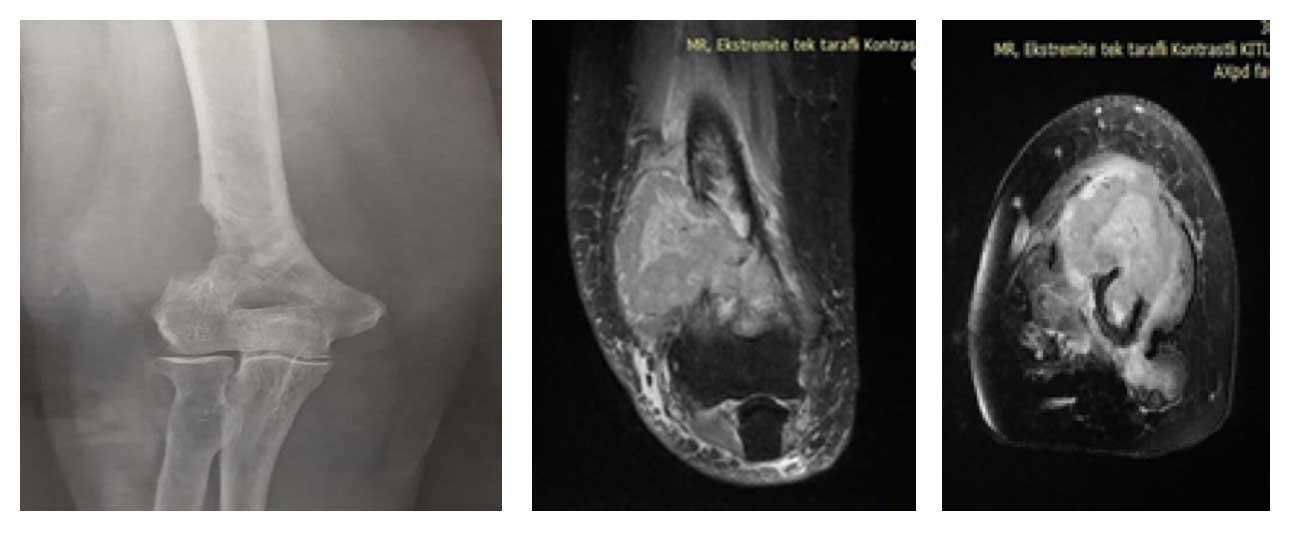

Ameliyat Öncesi: Röntgende sağ humerus alt dış kısımda kemik harabiyeti, MR’da kemiğin dışına çıkan büyük boyutta tümör kitlesi görülmekte.